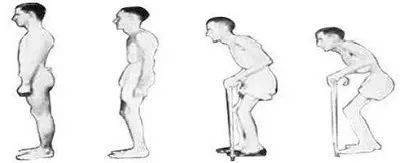

成都强直专科医院指出处于中期或晚期的强直患者关节骨骼已经 ...

下腰痛和脊柱僵硬:这是强直性脊柱炎的症状中较明显的一点。下腰 ...

强直性脊柱炎是一种慢性炎症性疾病,主要累及骶髂关节、脊柱、 ...